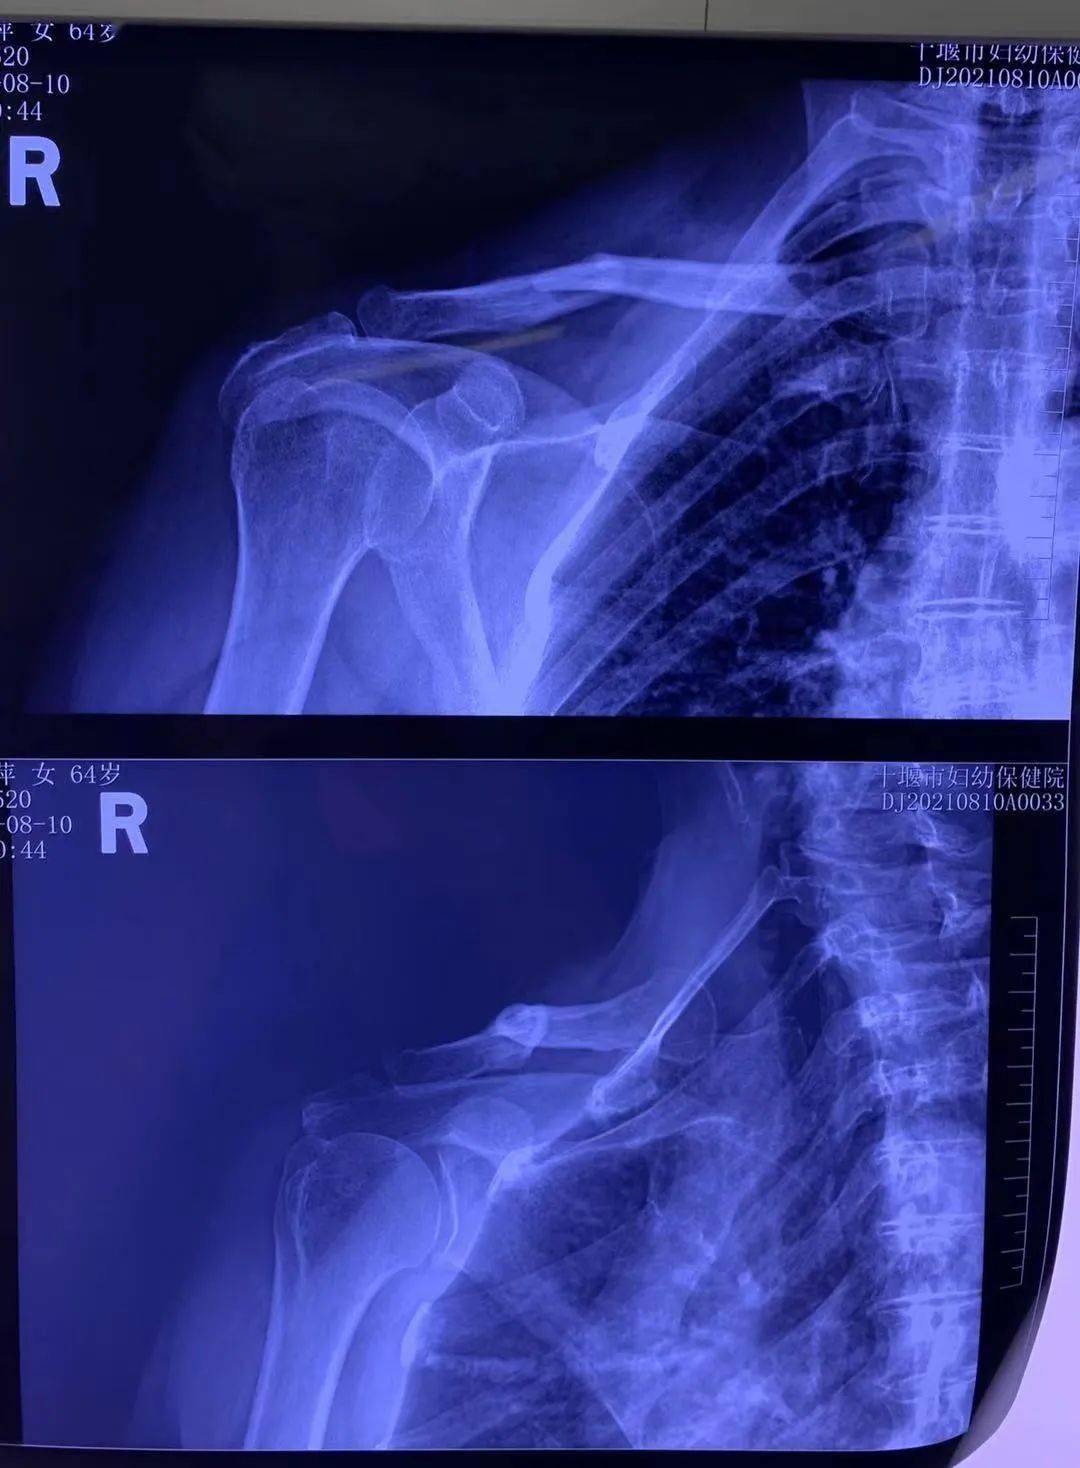

十堰市妇幼保健院成功开展锁骨骨折切开复位钢板内固定术

图片尺寸1080x1468